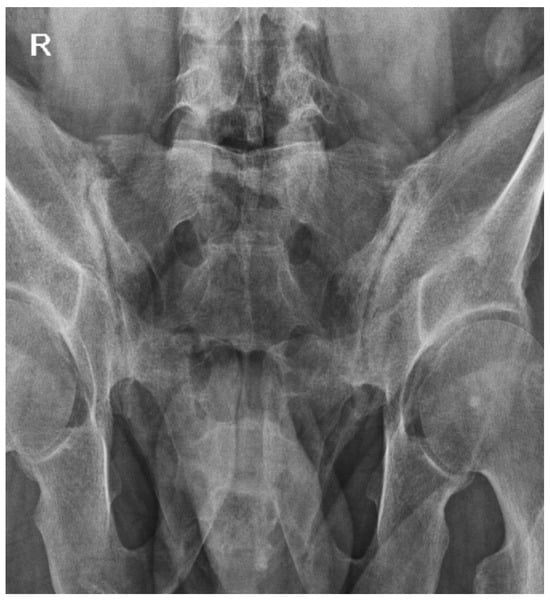

2.4. October 2023

2.5. Current Status and Follow-Up (March–October 2024)